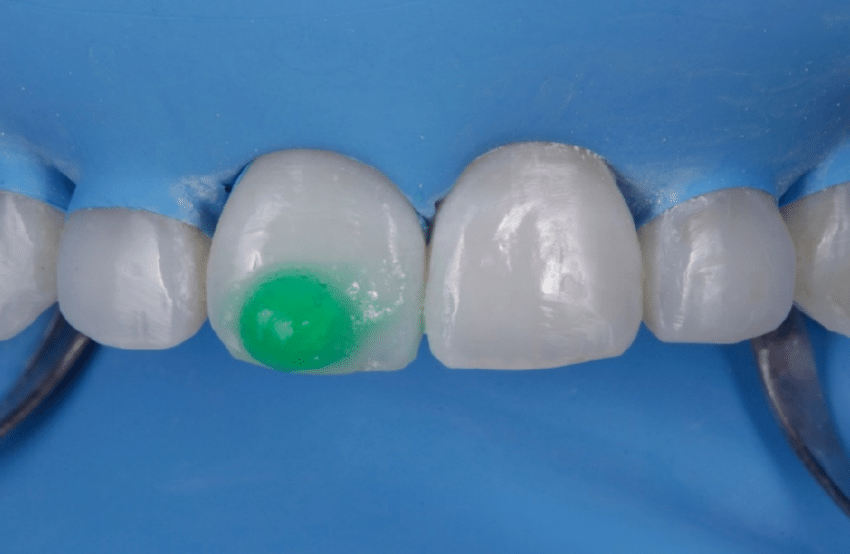

Aplicación de la resina infiltrante: La aplicación de la resina ICON en el diente puede llevar alrededor de 1-3 minutos, dependiendo de la extensión de las lesiones y la habilidad del dentista. Antes de aplicar la resina se puede «previsualizar» el resultado gracias al ayuda del Ethanol, que nos permite ver si el acido ha podido penetrar en Durante este tiempo, el dentista aplica cuidadosamente la resina en el diente afectado.